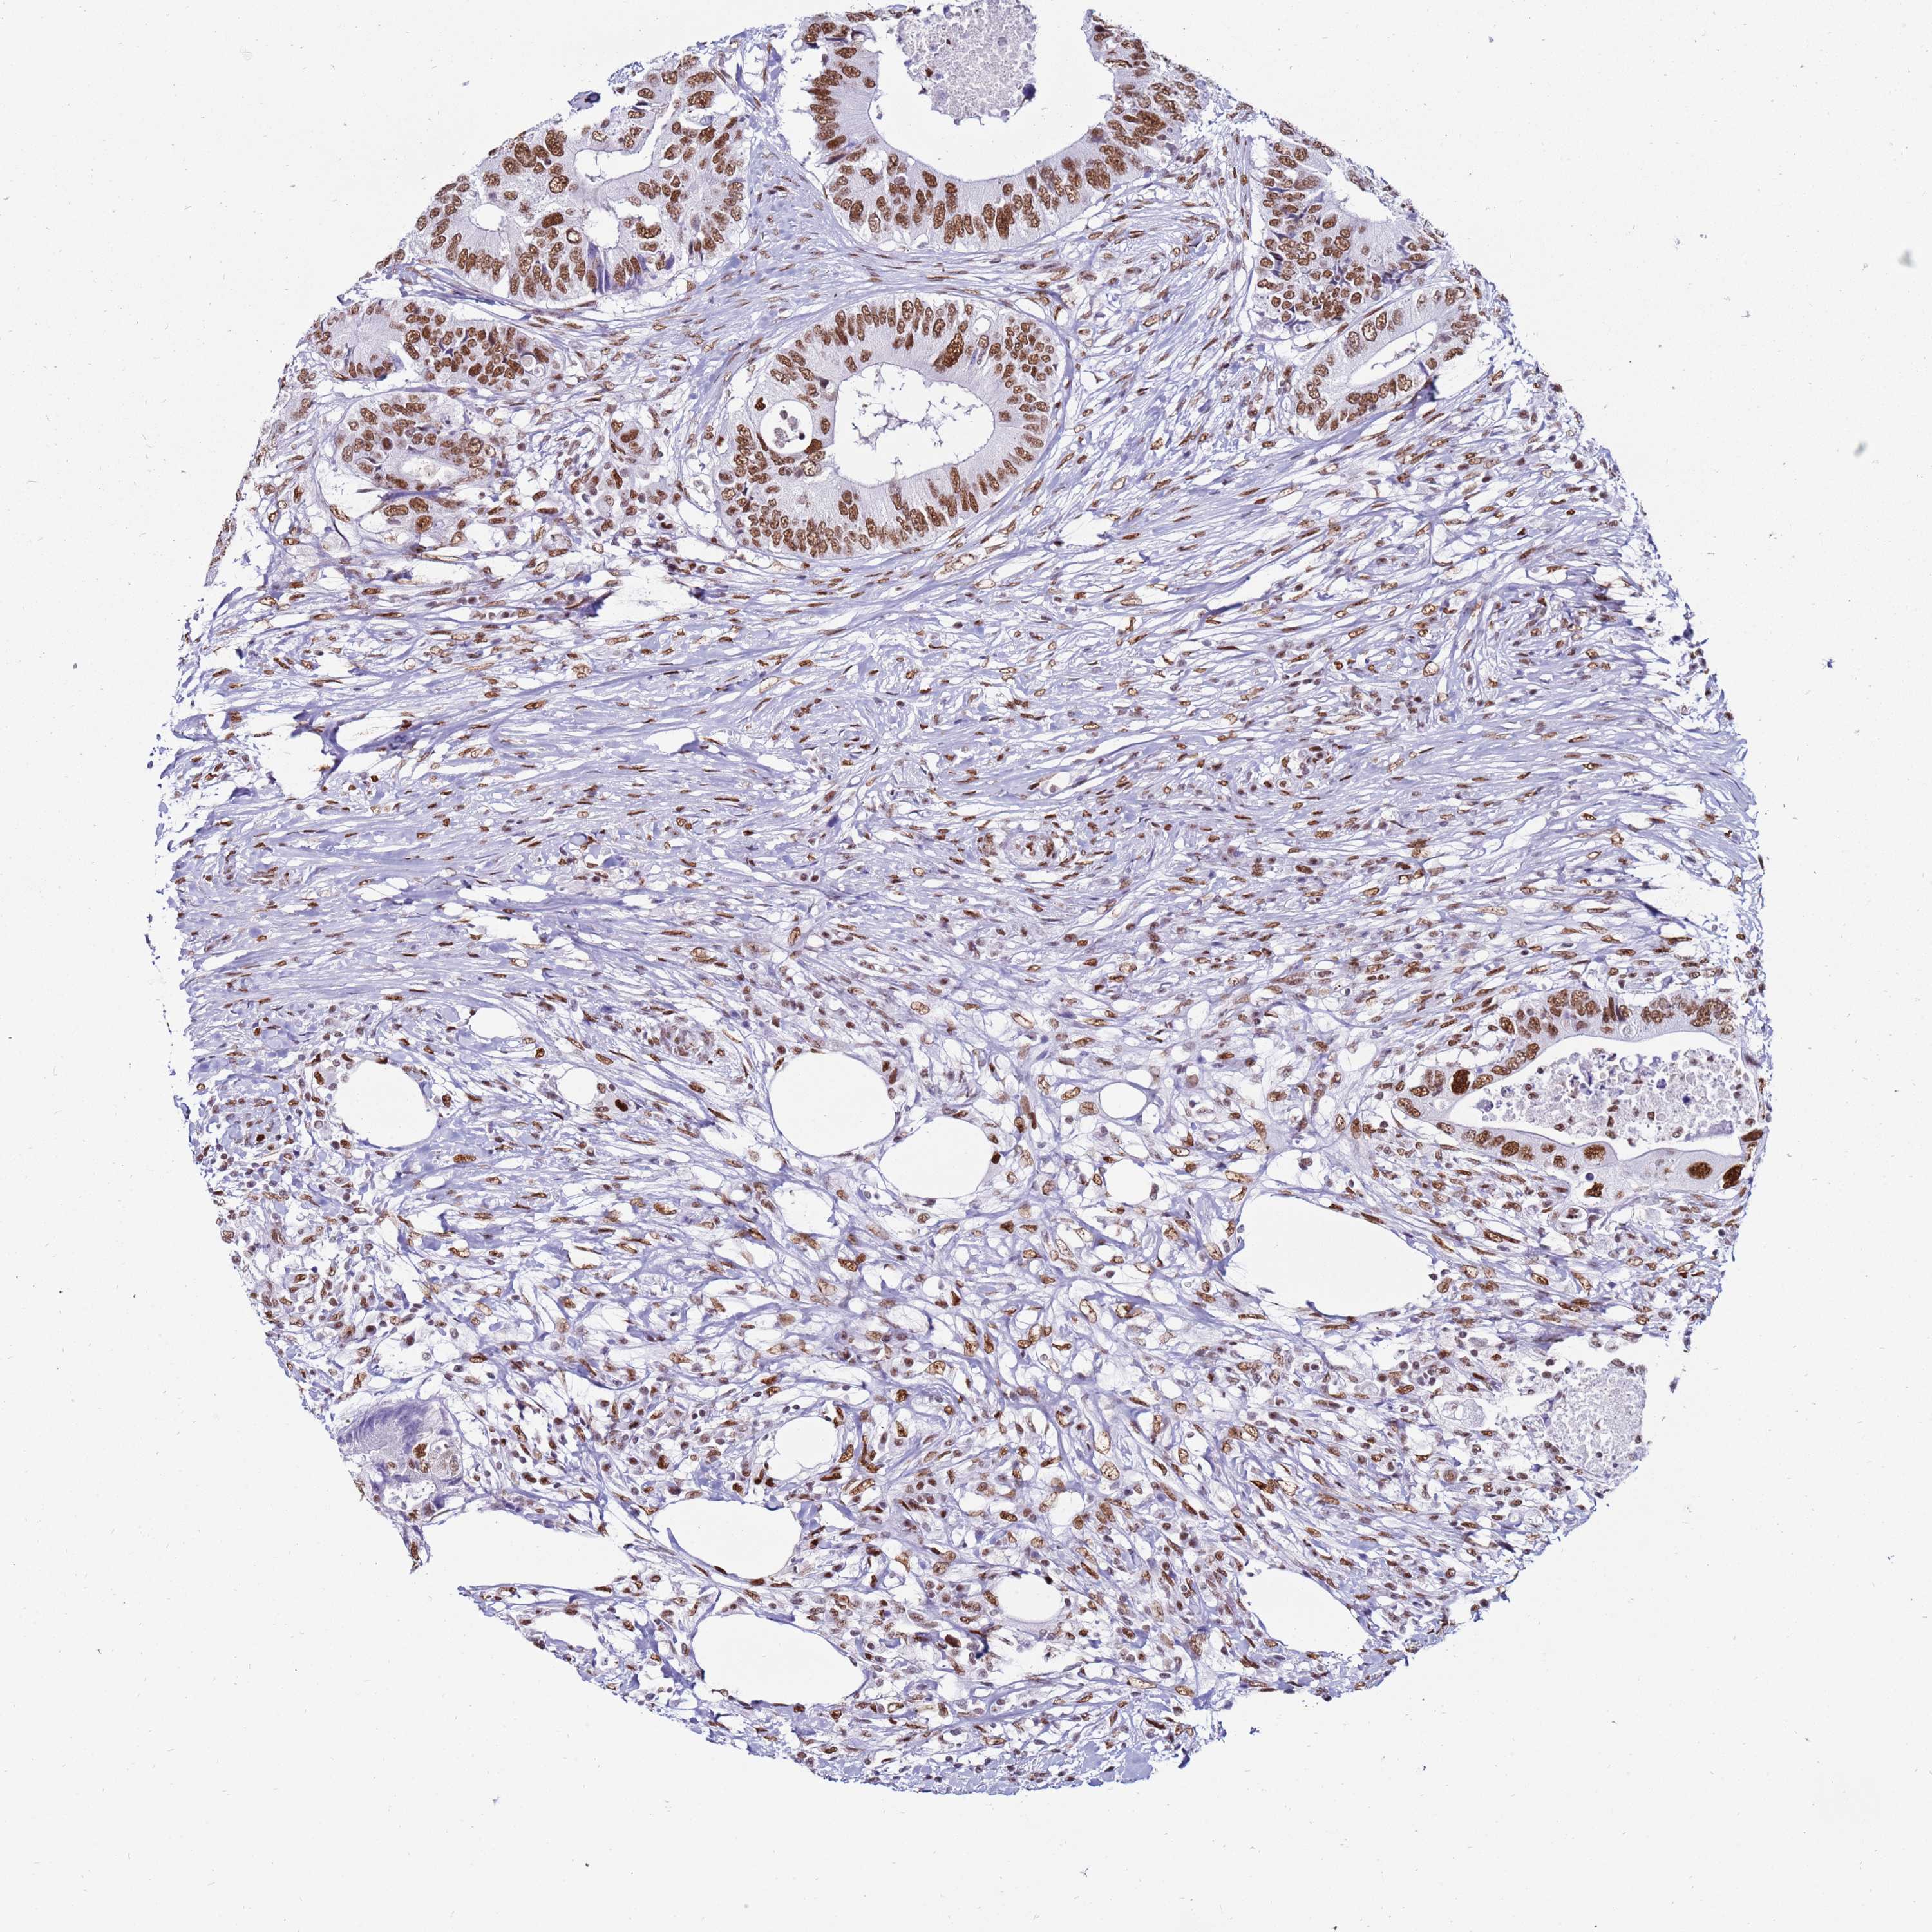

CANCER COLORECTAL CANCER Show tissue menu

Colorectal cancer

Human cancer

Colon adenocarcinoma